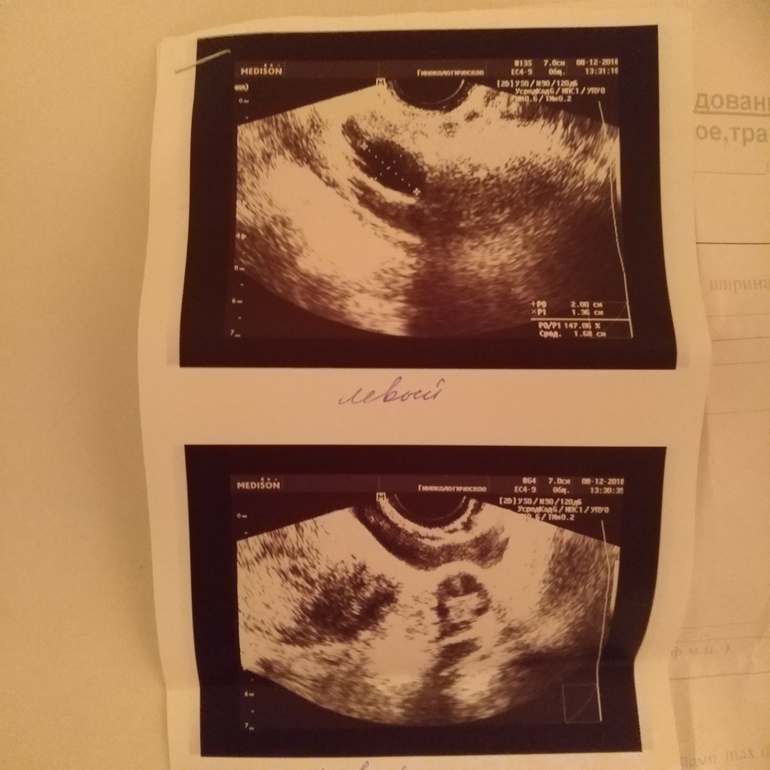

Добрый вечер. Недавно спрашивала поводу болей с левой стороны, подозревая кисту фолликулярную. Вот что увидели по УЗИ. Похоже на фолликул? И когда можно предположить овуляцию?

Сегодня-Завтра может случиться овуляция, у меня овулирует на 21-22 мм.

Да нет, в день УЗИ он у Вас уже был 20мм.

А я посмотрела что написано у Вас на листочке УЗИ, там в левом написано 20мм - это означает сегодня-завтра (в частности бы значило для меня). Надеюсь Вы со вчерашнего дня мучаете своего мужа, сегодня и завтра мучайте его 😂

Эндометрий 8мм, ЛЯ 3,2 х 1,4, диаметр 2,0 х 1,4

ПЯ 2,6х1,3, диаметр 1,0х 0,9